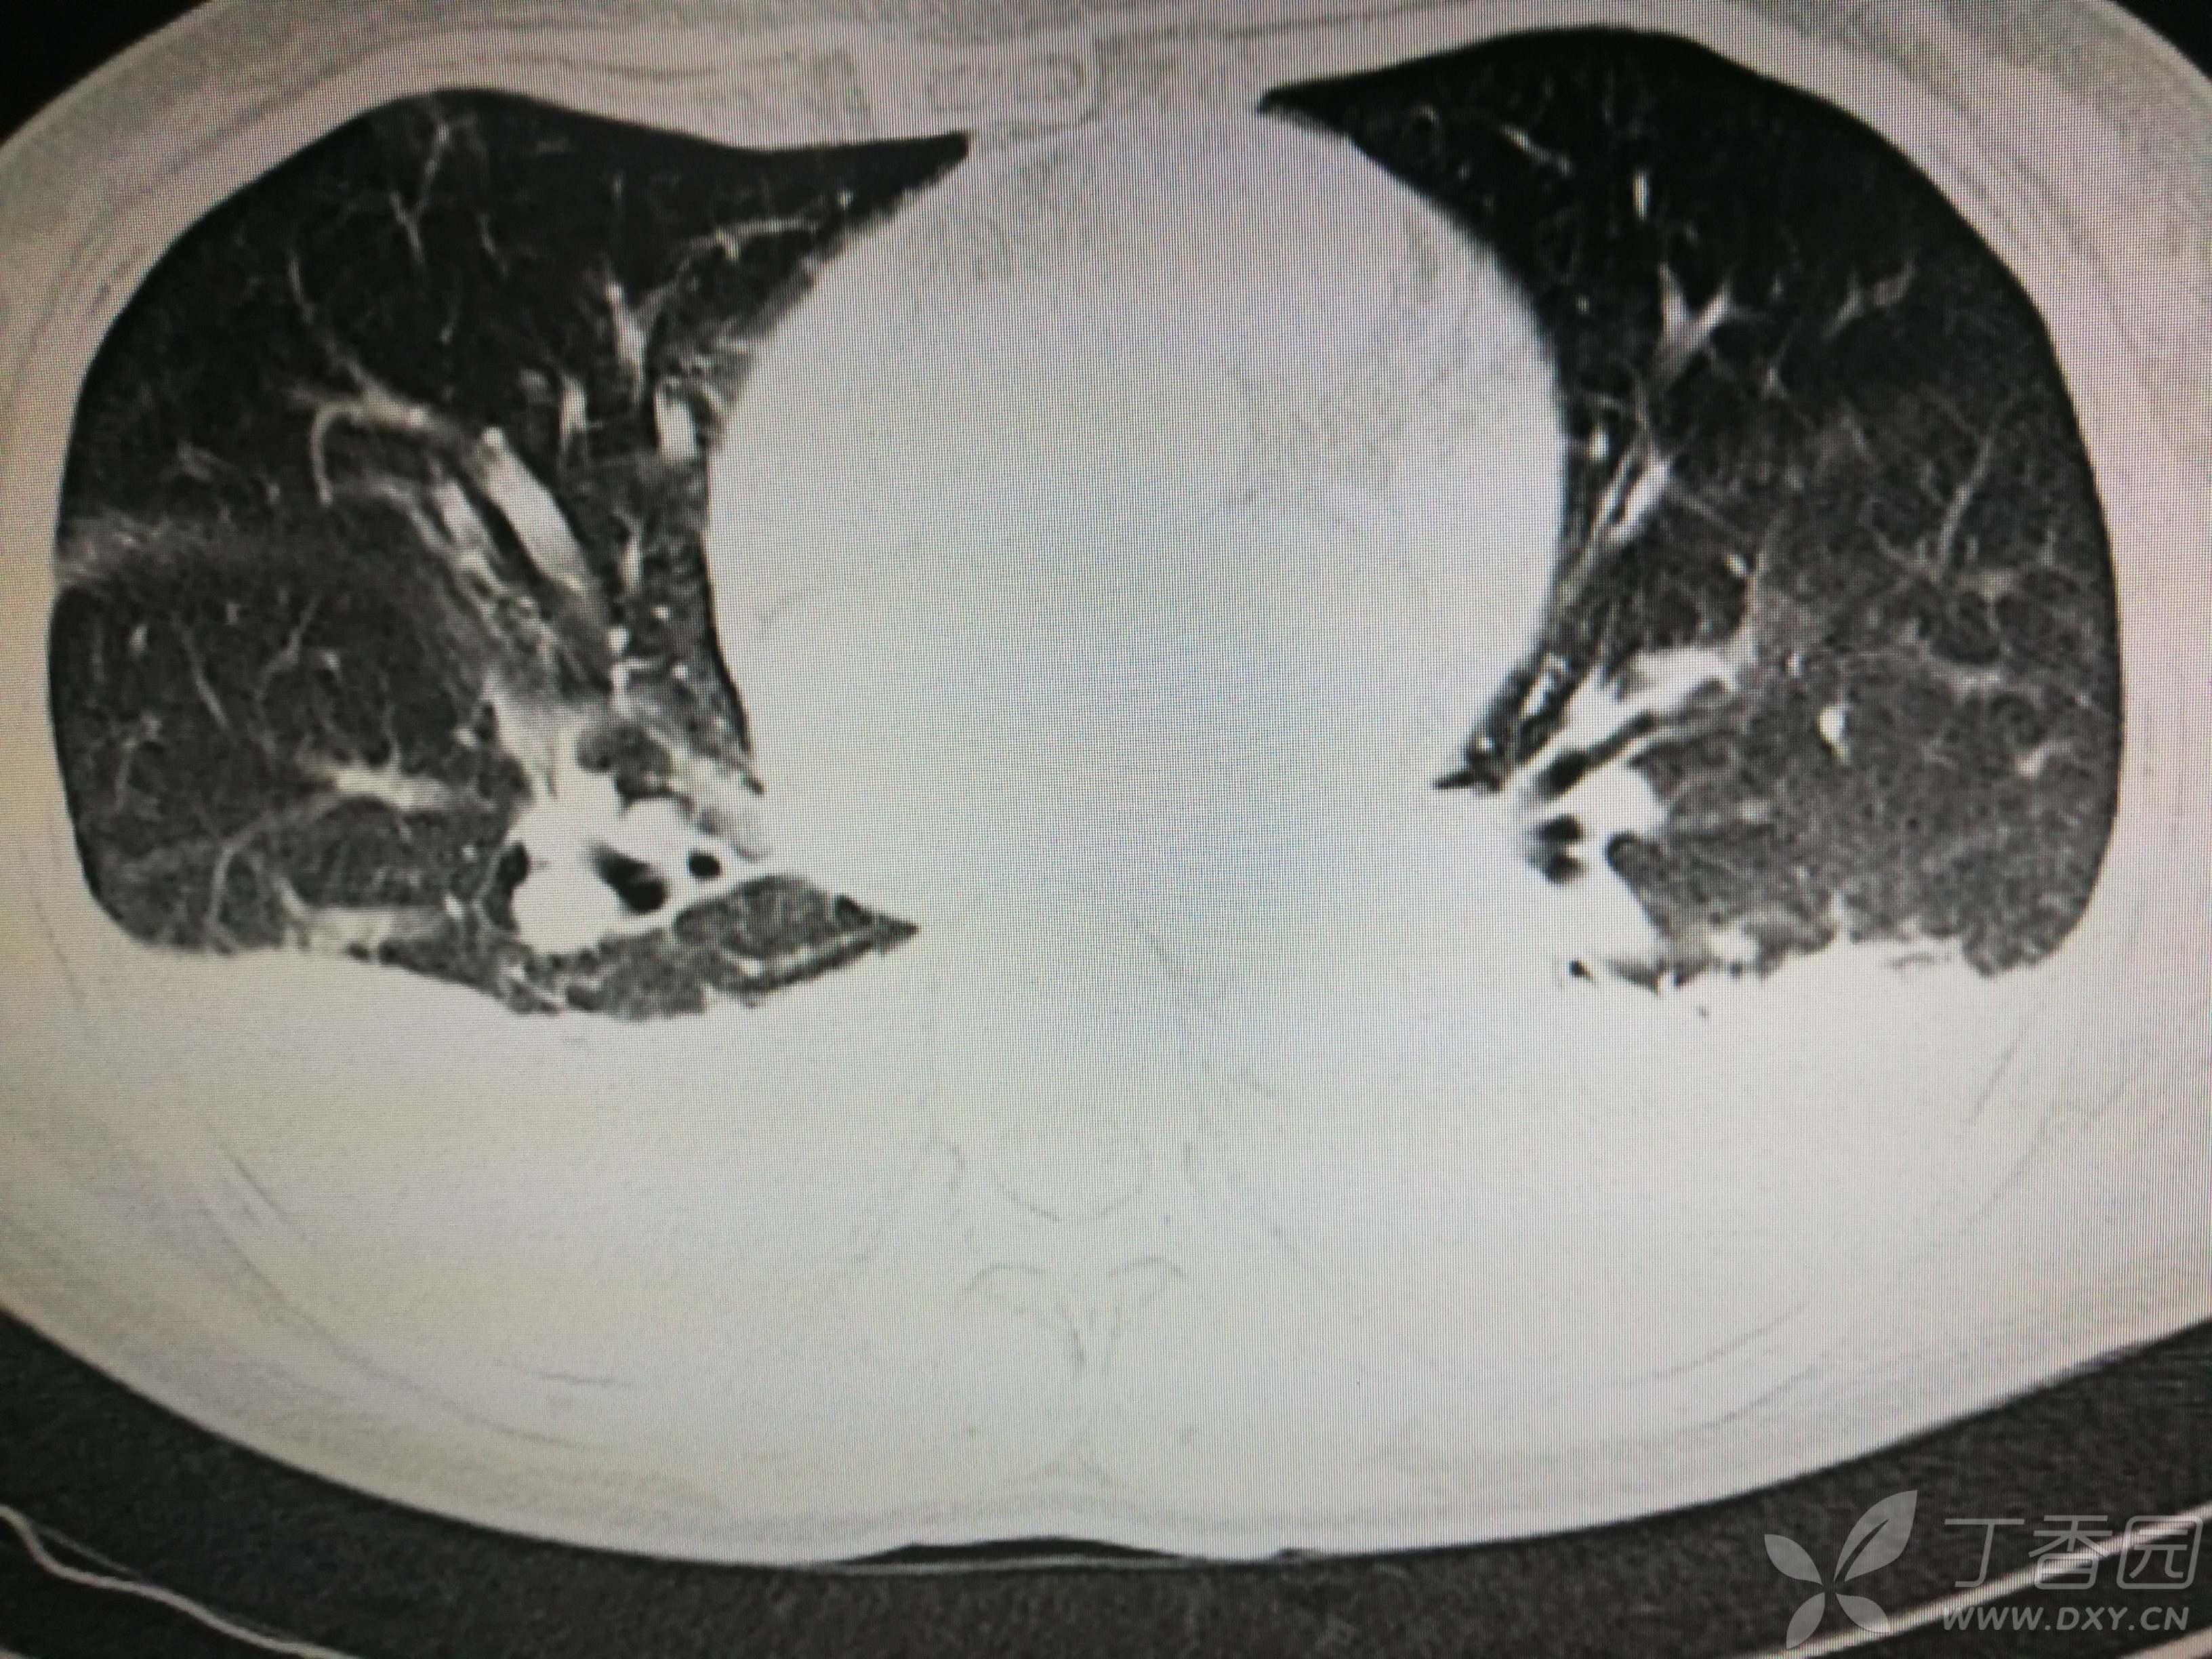

给予低分子肝素钙针抗凝、七叶皂苷钠针消肿及骨牵引固定等等治疗。入院后第四天行“左侧股骨下段骨折切开复位内固定术”(术前查双下肢彩超:双下肢深静脉血流通畅),手术顺利,术后予预防感染、预防血栓形成等治疗。术后患者无明显发热,生命体征平稳。术后第四天复查血常规:白细胞13.4×109/L,血红蛋白84g/L,血小板在正常范围。生化:白蛋白35.7g/L,余无明显异常。当天,患者开始出现轻度胸闷气急,可耐受。术后第五天患者胸闷气急加重,无胸痛,无背痛,无咯血,无意识障碍,无头晕头痛,无恶心呕吐等,急查凝血功能:纤维蛋白原降解产物12mg/L,D二聚体4000ug/L,余无明显异常。查动脉血气分析:pH7.52,氧分压62mmHg,二氧化碳分压30mmHg,碱剩余1.8mmol/L,乳酸1.0mm/L,血红蛋白86g/L。查胸部CT见下(先视频后图片):